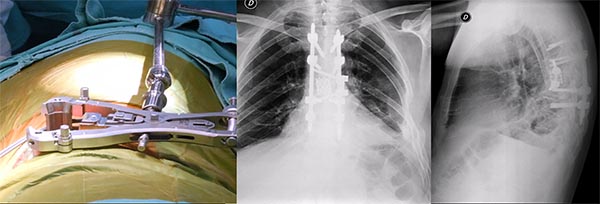

Figura 2:

Caso 24. A y B: Fractura horizontal que compromete cuerpo, pedículo izquierdo y apófisis espinosa de L1 (L1: B1; N1 AOSpine). C y D: Estabilización percutánea T12-L2.

Figura 3:

Caso 24. A: Fractura L1: B1; N1. B: Control 7 meses que evidencia consolidación. C y D: Retiro de osteosíntesis a los 9 meses con buena movilidad en las radiografías dinámicas de control.